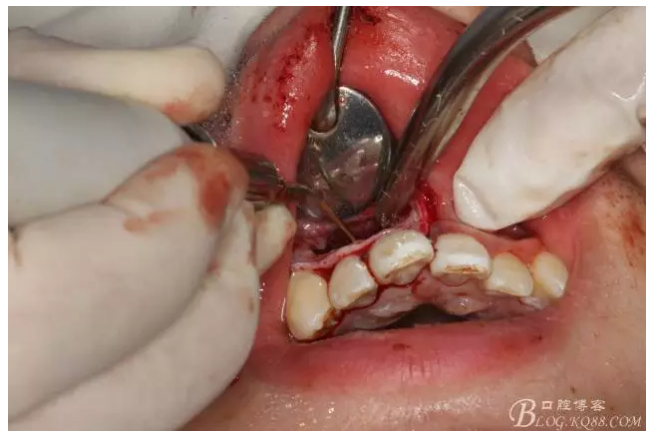

圖10.超聲骨刀去除的牙膠

圖11.MTA倒充填預(yù)備好的根尖3mm。

圖12.倒充填完畢的12根尖區(qū)影像